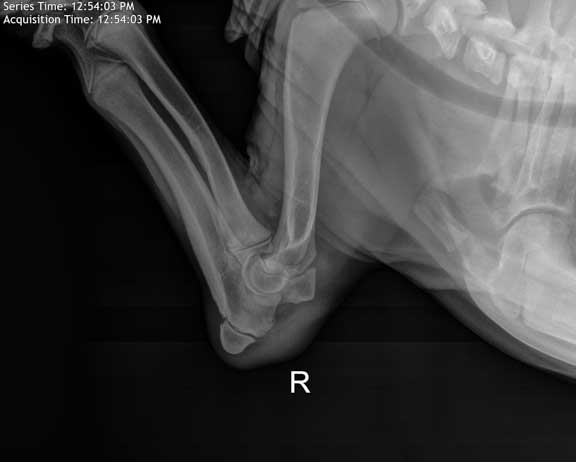

Elbow Dysplasia

The elbow of young dog showing where elbow dysplasia occurs and where it is diagnosed